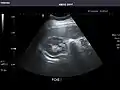

Right kidney

Kidneys: Right and left kidneys measure 11.5 cm and 12 cm in length respectively. No hydronephrosis. Small left lower pole kidney cyst.